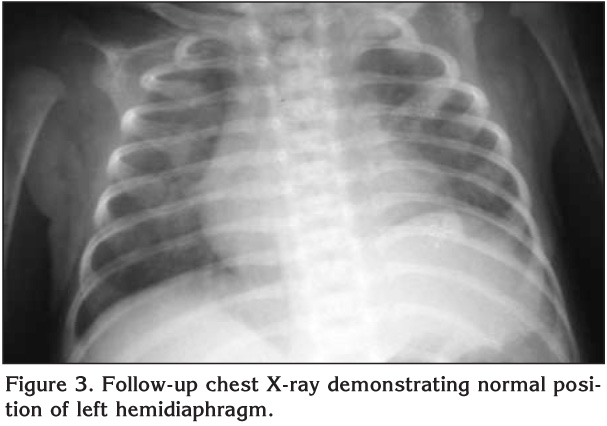

Figure 1

On the 26th day chest tube was replaced depending on the attempts to wean the patient from the ventilator were unsuccessful. He appeared distressed and hypoxic even on continuous positive airway pressure. On physical examination breath sounds were absent over the lower half of the left chest. Chest X-ray showed elevation of the left hemidiaphragm and ultrasonography of the diaphragm demonstrated absent movement during spontaneous breathing (Figure 2). The infant underwent to thoracotomy and plication of the left hemidiaphragm. He was successfully extubated on the second postoperative day. After three days of nasal continuous positive airways pressure, he subsequently required only 25% of supplementary oxygen. A chest X-ray 3 weeks later showed reexpansion of the left lung with normal diaphragmatic position (Figure 3). He was eventually discharged to home at 38 days of age.